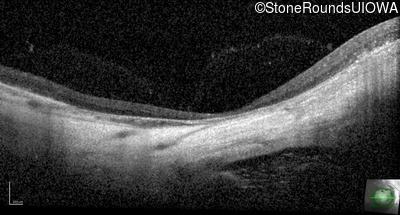

Infrared Fundus Photograph - Left - 20/100

Exemplar